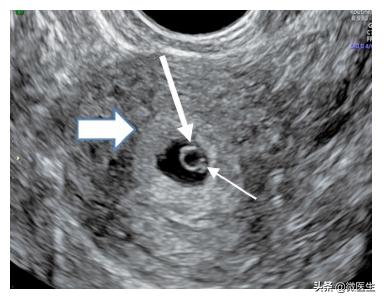

随着妊娠进展,绒毛与子宫蜕膜形成特征性的“双环征”(下图)。经腹部超声在孕5~6周发现,经腔内超声在孕4~5周发现。

孕38天,经腔内超声检查显示“双环征”(粗箭头)、孕囊、卵黄囊(长箭头)及胎芽(细箭头)随着孕周増加。

妊娠囊可为椭圆形、不规则形等需与假妊娠囊(宫腔积液)鉴别,宫腔积液无“双环征”,形态与宫腔一致,位于宫腔中央,周边强回声为分离的子宫内膜。